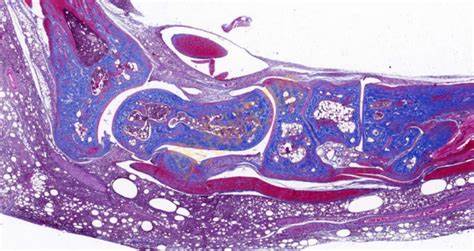

免疫组化(Immunohistochemistry,IHC)是一种利用抗原 - 抗体特异性反应来定位和定性组织细胞中特定抗原的技术,在病理学、肿瘤学等众多领域发挥着关键作用。**一、原理**1. 抗原 - 抗体反应 - 基于抗原与抗体之间的高度特异性结合。组织细胞中的蛋白质、多肽等抗原成分能够被相应的特异性抗体识别并结合

4008386992 立即咨询免疫组化(Immunohistochemistry,IHC)是一种利用抗原 - 抗体特异性反应来定位和定性组织细胞中特定抗原的技术,在病理学、肿瘤学等众多领域发挥着关键作用。

特殊染色是病理学和组织学中使用的一种染色方法,用于显示组织或细胞中的特定成分,这些成分在常规的苏木精 - 伊红(HE)染色中可能无法清晰地显示。以下是关于特殊染···...